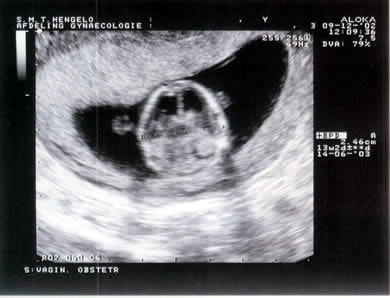

Bovenkant hoofdje

Duidelijk te zien het word een kindje!gyn wees ons nog op aanwezigheid neusbotje,bij kindjes met down was die afwezig

Nekplooi meting,ook goed